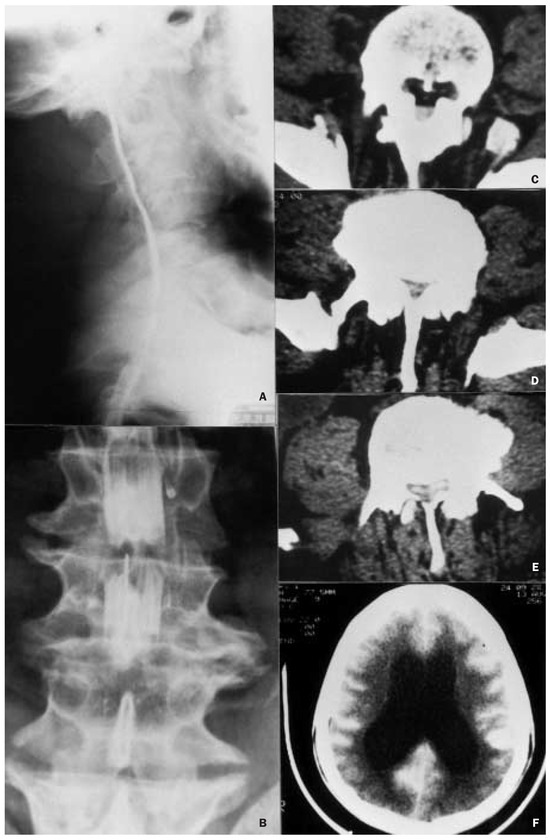

Severe neurological complications in an adult achondroplastic dwarf with generalised spinal stenosis

by P. J. Fournier, M. Aguilar and S. Stephanov

Swiss Arch. Neurol. Psychiatry Psychother. 2004, 155(2), 64-66; https://doi.org/10.4414/sanp.2004.01459 - 1 Jan 2004

A case is reported with generalised spinal stenosis and severe neurological complications.Neurological and radiological findings and surgical procedures are discussed. The patient was admitted with profound spastic lower paraparesis and the upper limbs were paretic. After an emergency lumbar decompression, the patient improved [...] Read more.

A case is reported with generalised spinal stenosis and severe neurological complications.Neurological and radiological findings and surgical procedures are discussed. The patient was admitted with profound spastic lower paraparesis and the upper limbs were paretic. After an emergency lumbar decompression, the patient improved and on the twelfth day he was able to take a short walk.Twenty-two days after the lumbar decompression a cervico-thoracic decompression was performed which proved fatal. Full article

Show Figures

Figure 1